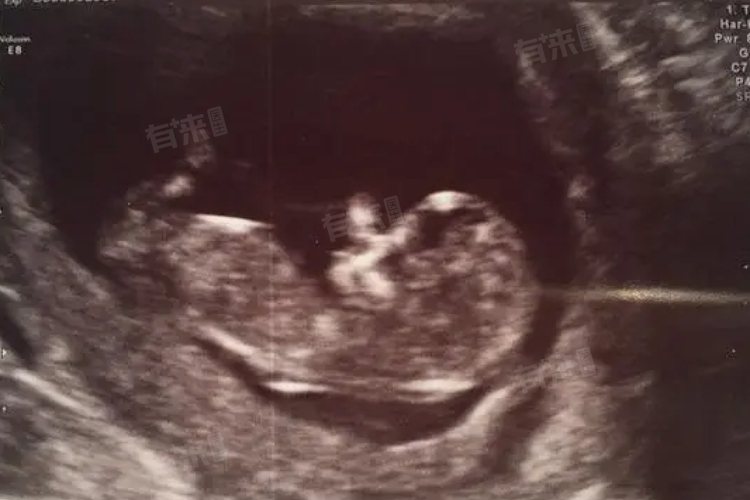

- 产科领域的三维彩超检查价格相对较高,通常在500-2000元范围内。这一区间的差异主要源于检查目的的特殊性:孕中期的胎儿畸形筛查需要对胎儿全身进行系统评估,设备需具备高分辨率成像能力,且检查耗时较长,导致综合成本上升。此外,部分医疗机构提供的胎儿心脏专项三维超声检查,因技术要求更高,费用可能达到800-1500元。

2、检查时间选择:孕期三维彩超的最佳时间是孕22-26周,此时胎儿发育较为完善,羊水量适中,图像清晰度较高。